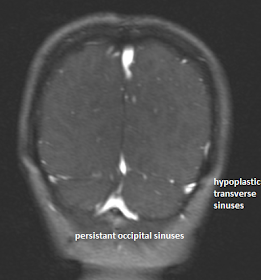

| Abnormal sinuses seen originating from torcula heterophili and coursing posterolaterally. |

| The sinuses are joining the internal jugular veins bilaterally. |

Occipital sinuses usually communicate cranially at the torcular

Herophili and caudally at the foramen magnum, where a multitude of variations

may exist.

Occipital sinuses have been reported in up to 10% of normal

subjects and may be associated with atretic transverse/sigmoid sinus segments

and internal jugular vein. Correlation with CT may bolster confident diagnosis

by demonstrating a smaller caliber sigmoid sinus groove and/or jugular foramen.